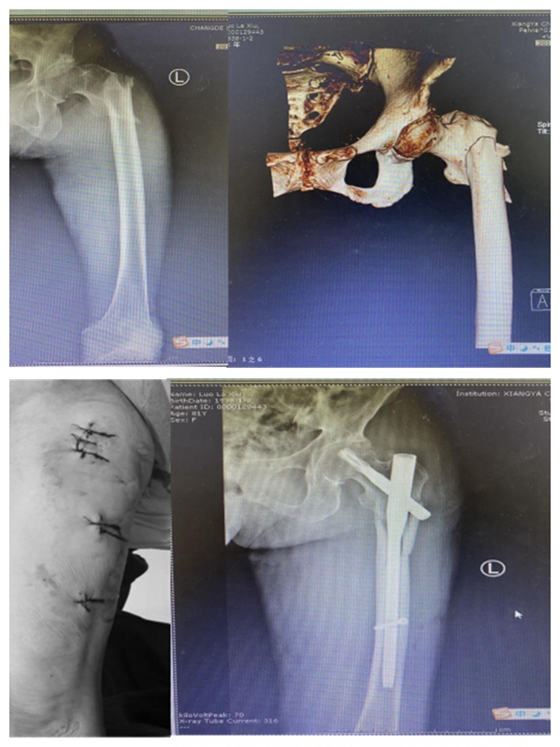

患者:罗某,86岁

湘雅常德医院开院以来,主要收治的髋部骨折患者年龄从70-102岁不等,且多伴有心肺功能不全,合并多种内科疾患,具有手术风险高、难度大的特点。在科主任张朝跃主任医师和创伤组长王穗源副主任医师的带领下,与全院各临床科室、麻醉、手术部进行多学科合作,开展了一系列针对高龄及超高龄患者的髋部骨折个性化手术治疗,术后2-3天即可扶助下地行走,患者及家属满意度极高,极大地减轻了老年患者的痛苦,延长了患者的生命,减轻了家庭护理负担,获得了良好的社会口碑。